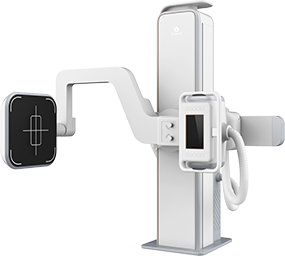

Intermedical est une société italienne spécialisée dans la conception et la fabrication de systèmes de radiologie mobiles et fixes. Elle met l’accent sur l’innovation et les technologies numériques modernes afin d’offrir des solutions d’imagerie précises, fiables et simples d’utilisation pour les hôpitaux et centres médicaux du monde entier.